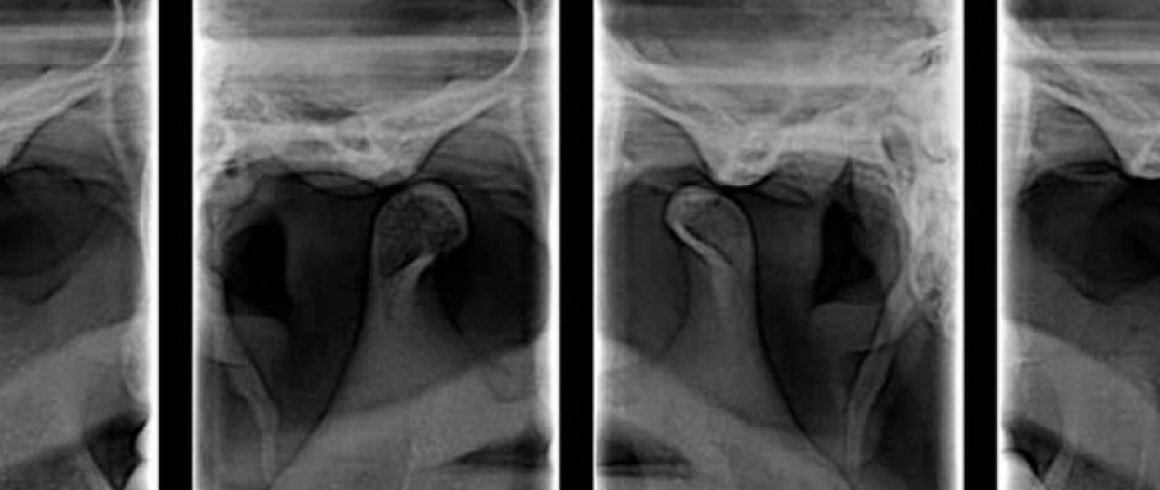

- A.T.M.

- A.T.M. (Boca abierta/Boca cerrada)